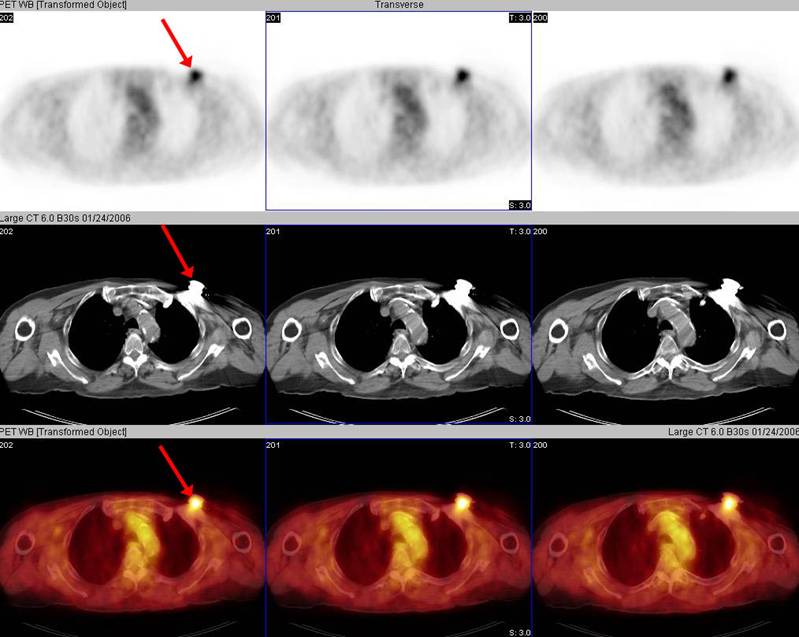

There is intense activity in the left upper chest wall which correlates exactly in location with a metallic density pacemaker.

Because of the significantly higher density of metallic hardware compared to normal body tissues, the PET attenuation correction process "overcorrects" the PET images, essentially "adding in" activity to the tissues containing the hardware. This is because photons originating in these locations (if there were any) would be markedly attenuated by the metal. Of course, in the exact location of the hardware the artifactual activity "added in" does not pose a problem because it can be attributed to the hardware itself by close inspection of the CT data. However, the activity artifactually "added in" can include tissues closely approximated to hardware (such as muscles or lymph nodes) and this can pose a diagnostic dilemma. Therefore, the non-attenuation-corrected data should always be inspected in addition to the attenuation-corrected data. This will often elucidate whether there is any truly increased activity located within tissues adjacent to hardware. However, in some cases artifacts related to hardware preclude definitive evaluation of activity within adjacent tissues and other means of assessment are needed.

The non-attenuation-corrected data shown in the bottom row confirms that there is actually no increased activity in the left upper chest wall, as was apparent on the attenuation-corrected data shown in the top row. The attenuation correction process resulted in artifactually increased activity in the region of the metallic density pacemaker.